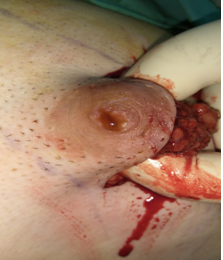

Πορογενές καρκίνωμα ανδρικού μαστού. Αιματηρή έκκριση θηλής. Ταχεία βιοψία (Ευγενική παραχώρηση Dr. V. Penopoulos)